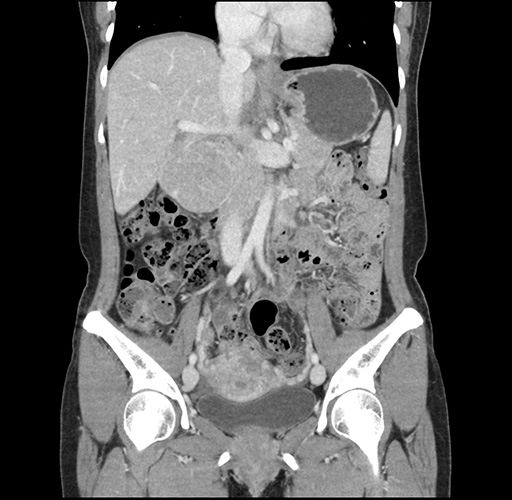

Imaging Analysis

Look through the patient's CT scan to identify any areas of concern for the necessary procedure.

Based on your CT findings, which issue(s) would give reason for "planned slowing down moment(s)" in this case?

Considering a standard left lateral sectionectomy procedure, what step(s) of the operation would you do differently in this case ?